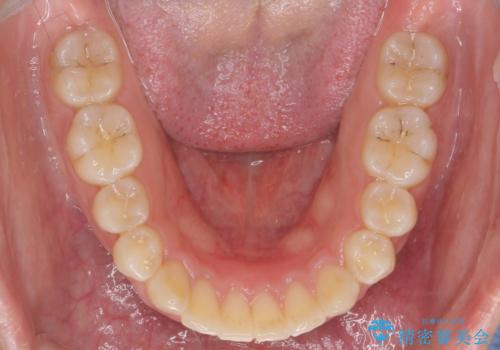

深い噛み合わせ、すきっ歯の改善 ワイヤーを用いたマルチブラケット矯正

- 噛み合わせが深く、前歯が突き出て隙間が出てきたことの改善を希望され矯正治療の相談で当院に初診来院されました。

ワイヤーを用いたマルチブラケット矯正を行うことで深い噛み合わせを改善し、前歯の隙間もなくし審美的な歯列へと治療をおこなっていきます。

深い噛み合わせの改善は前歯の圧下が必要なため、治療期間が長期化することが多いです。